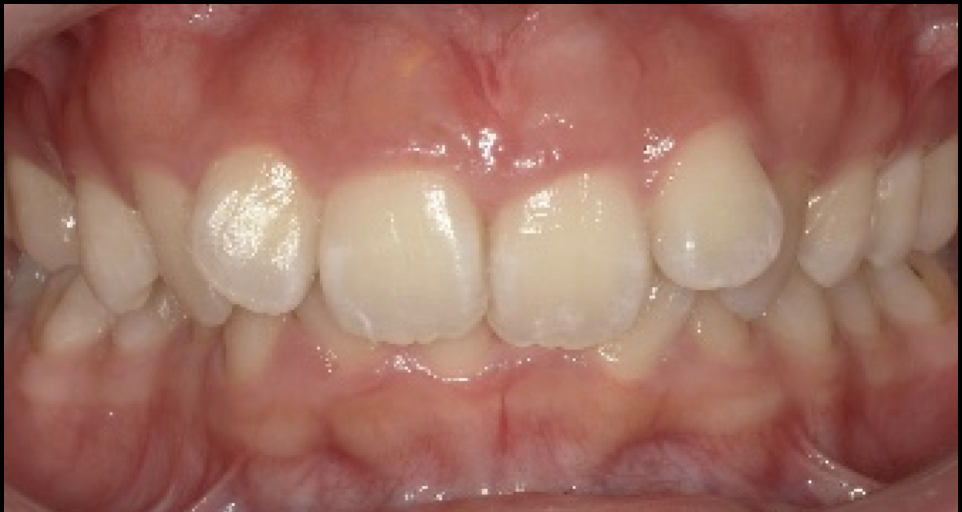

空隙歯列・スリーインサイザルを咬合から整え、審美修復で改善した症例

- 担当医

- 生野誠

- 主訴

- 噛み合わせが安定しない

顎が痛い

- 期間

- 3年

- 費用

- 150万

- 治療内容

- 部分矯正

ダイレクトボンディング

ラミネートベニア

接着性ブリッジ

テーブルトップベニア

- 治療に伴うリスク

- 後戻り

セラミックの破折